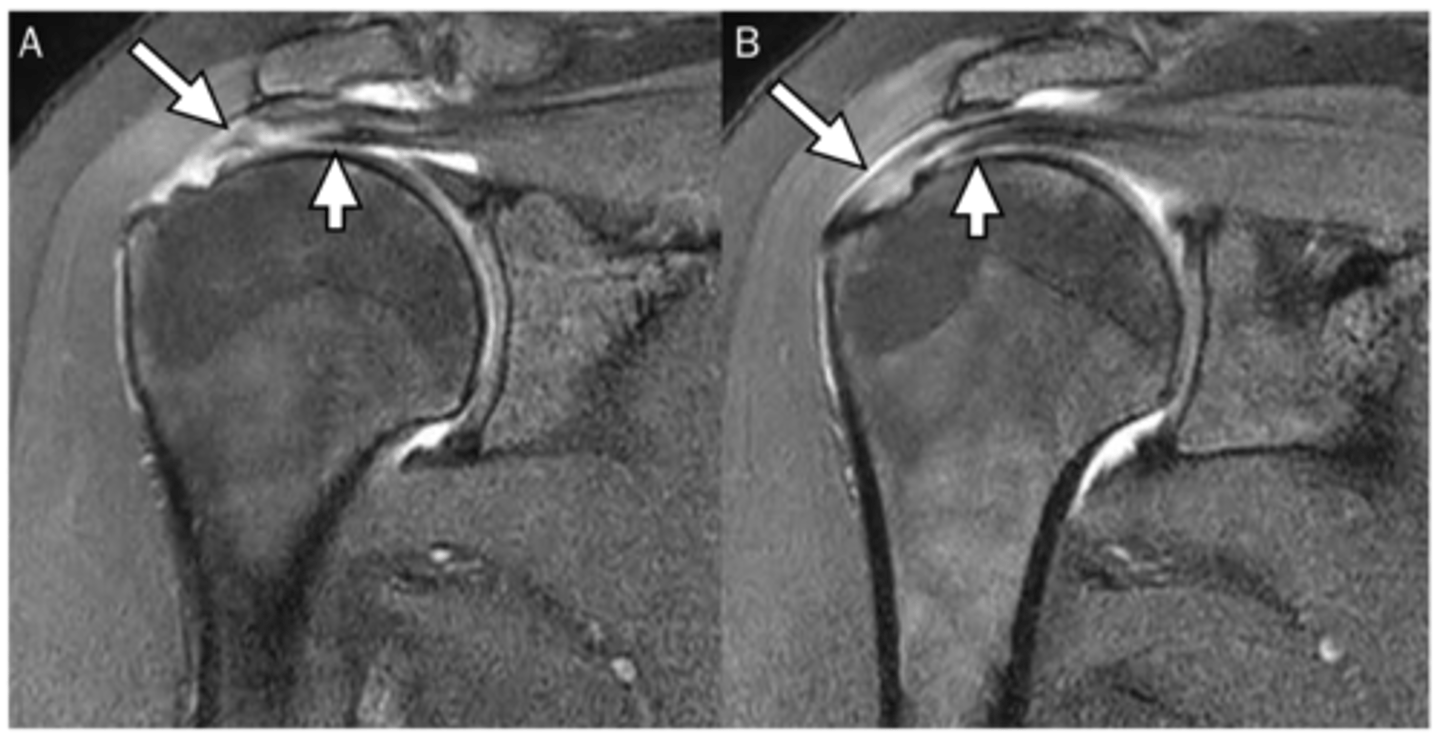

Complete thickness tear of the supraspinatus w/ major bucking and retraction as the muscle pulls the tendon back

What are these images depicting w/ the rotator cuff?